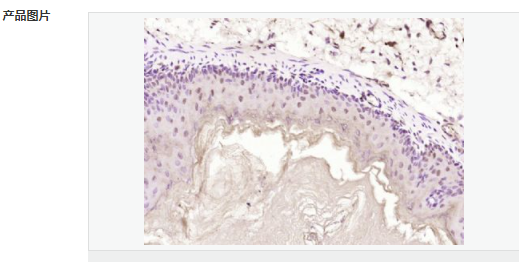

| 产品应用 | WB=1:500-2000 ELISA=1:5000-10000 IHC-P=1:100-500 IHC-F=1:100-500 ICC=1:100-500 IF=1:100-500 (石蜡切片需做抗原修复) not yet tested in other applications. optimal dilutions/concentrations should be determined by the end user. |

| 产品介绍 | Machado-Joseph disease, also known as spinocerebellar ataxia-3, is an autosomal dominant neurologic disorder. The protein encoded by this gene contains (CAG)n repeats in the coding region, and the expansion of these repeats from the normal 13-36 to 68-79 is one cause of Machado-Joseph disease. There is a negative correlation between the age of onset and CAG repeat numbers. Alternatively spliced transcript variants encoding different isoforms have been described for this gene. [provided by RefSeq, Sep 2009] Function: Interacts with key regulators (CBP, p300 and PCAF) of transcription and represses transcription. Acts as a histone-binding protein that regulates transcription. Acts as a deubiquitinating enzyme. Subcellular Location: Nucleus matrix. Predominantly nuclear, but not exclusively, inner nuclear matrix. Tissue Specificity: Ubiquitous. DISEASE: Defects in ATXN3 are the cause of spinocerebellar ataxia type 3 (SCA3) [MIM:109150]; also known as Machado-Joseph disease (MJD). Spinocerebellar ataxia is a clinically and genetically heterogeneous group of cerebellar disorders. Patients show progressive incoordination of gait and often poor coordination of hands, speech and eye movements, due to degeneration of the cerebellum with variable involvement of the brainstem and spinal cord. SCA3 belongs to the autosomal dominant cerebellar ataxias type I (ADCA I) which are characterized by cerebellar ataxia in combination with additional clinical features like optic atrophy, ophthalmoplegia, bulbar and extrapyramidal signs, peripheral neuropathy and dementia. The molecular defect in SCA3 is the a CAG repeat expansion in ATXN3 coding region. Longer expansions result in earlier onset and more severe clinical manifestations of the disease. Similarity: Contains 1 Josephin domain. Contains 3 UIM (ubiquitin-interacting motif) repeats. SWISS: P54252 Gene ID: 4287 Database links: Entrez Gene: 4287 Human Entrez Gene: 110616 Mouse Omim: 607047 Human SwissProt: P54252 Human SwissProt: Q9CVD2 Mouse Unigene: 532632 Human Unigene: 271914 Mouse Unigene: 42932 Rat Important Note: This product as supplied is intended for research use only, not for use in human, therapeutic or diagnostic applications. |